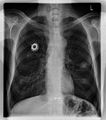

-

Röntgenaufnahme des Thorax (Projektionsbild)